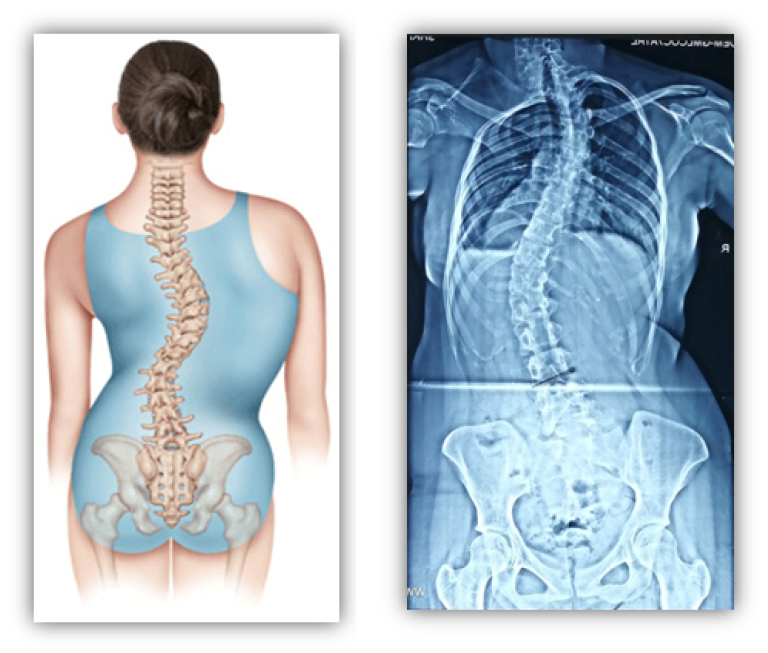

TAHUN BARU, KEBIASAAN BARU: MEMPERTAHANKAN KESADARAN BERPOSTUR UNTUK MENCEGAH PERTAMBAHAN KELENGKUNGAN TULANG BELAKANG PADA PENDERITA SKOLIOSIS

MITOS DAN FAKTA MENGEJUTKAN TENTANG SKOLIOSIS PADA ANAK DAN TERAPI SKOLIOSIS YANG EFEKTIF

SKOLIOSER BOLEHKAH BEROLAHRAGA? PANDUAN OLAHRAGA YANG COCOK UNTUK PENDERITA SKOLIOSIS